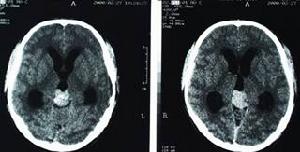

顱內壓增高綜合症 CT表現對疑有嚴重顱內壓增高,特別是急性,亞急性起病有局限性腦損害症狀的患者,切忌盲目腰穿檢查。只有在診斷為腦炎或腦膜炎和無局限性腦損害之蛛網膜下腔出血症,方可在充分準備後行腰穿檢查。